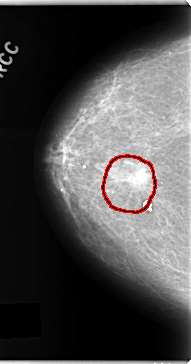

C_0156_1.RIGHT_MLO

FILE: C_0156_1.RIGHT_MLO.OVERLAY

TOTAL_ABNORMALITIES 1

ABNORMALITY 1

LESION_TYPE MASS SHAPE IRREGULAR MARGINS SPICULATED

ASSESSMENT 5

SUBTLETY 5

PATHOLOGY MALIGNANT

TOTAL_OUTLINES 1

BOUNDARY